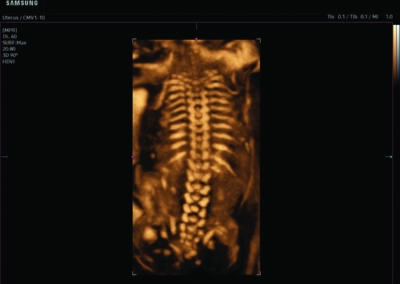

Comprehensive, advanced and expert MFM care for high-risk pregnancies

- Neural tube defects

- Fetal anomalies